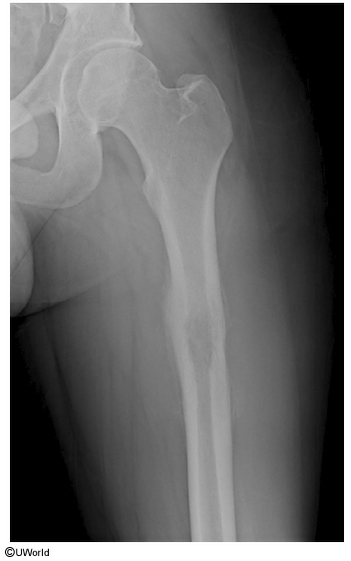

ewing sarcoma